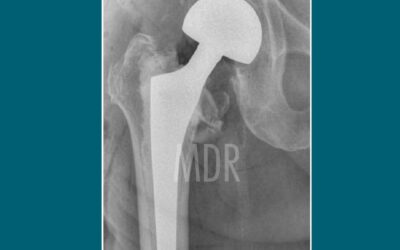

Caso de éxito en Paciente con Fractura de Cadera

Como Carmen, muchos pacientes recuperan movilidad y calidad de vida tras una cirugía de cadera. El Dr. Mario Dorantes Rodríguez ofrece atención especializada y un acompañamiento cercano en cada etapa de la recuperación.

¿Osteosíntesis o Prótesis?

Entiende la diferencia y cuándo se indica cada una. Cada paciente es diferente. Por eso, la valoración oportuna por un ortopedista experimentado es clave para elegir el tratamiento más seguro y funcional.